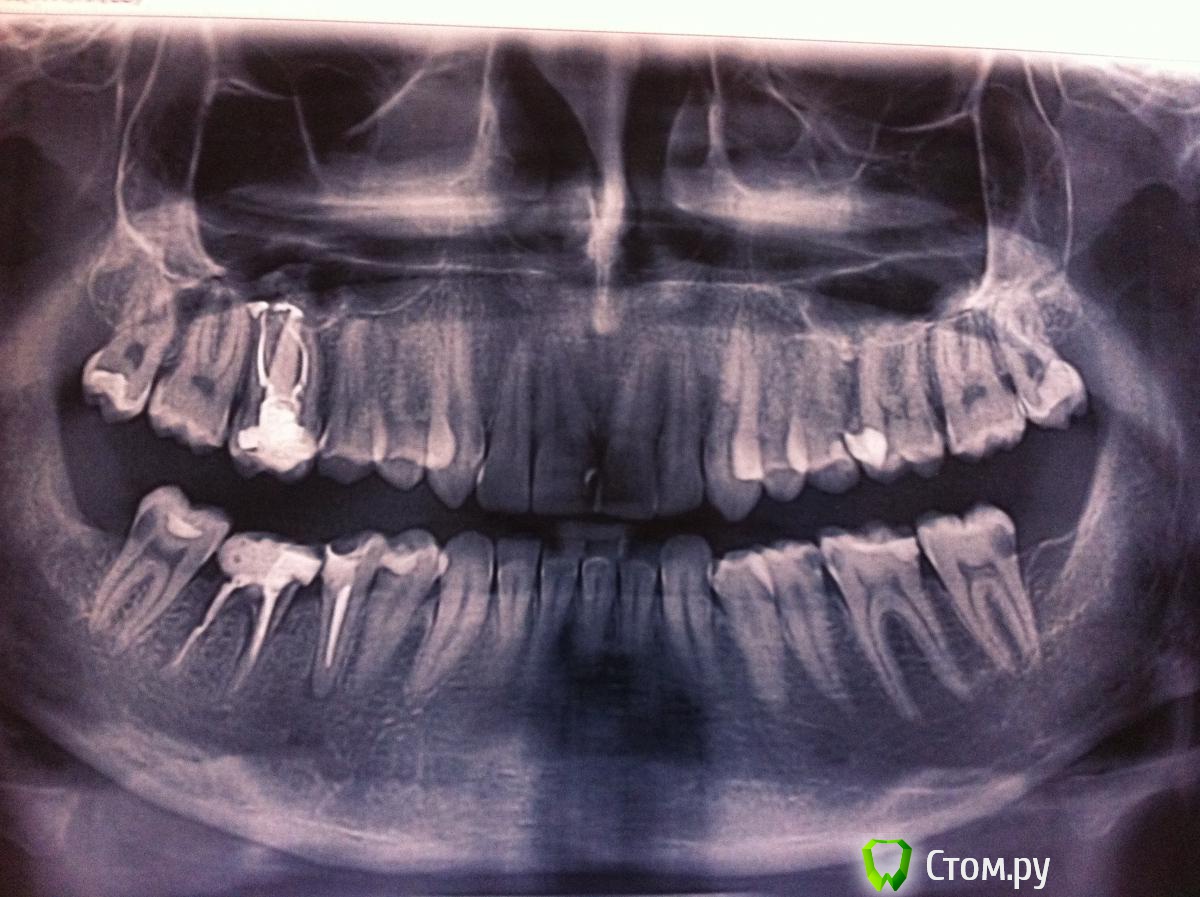

3.Дентально:

Слева 2 класс

Справа супер 2 класс

По сагитали: вч-ретрузия резцов

Нч протрузия резцов

По вертикали: глубокий прикус

По трансверзали:смещение ср линии на 3 мм вправо

Болтон 0.76 –размер нижних преобладает над верхними

Анализ дефицита

Вч медиодистальные размеры  7-7=123

Дуга=124

Нч медиодистальные=112

Дуга =111

2 скелетный класс,смещиение средней линии на 3 мм,глубокий прикус,ретрузия резцов вч,протрузия резцов нч,

Я про ретрогнатию разобрался только частично,но похоже у него ретрогнатия нч

Профиль вогнутый